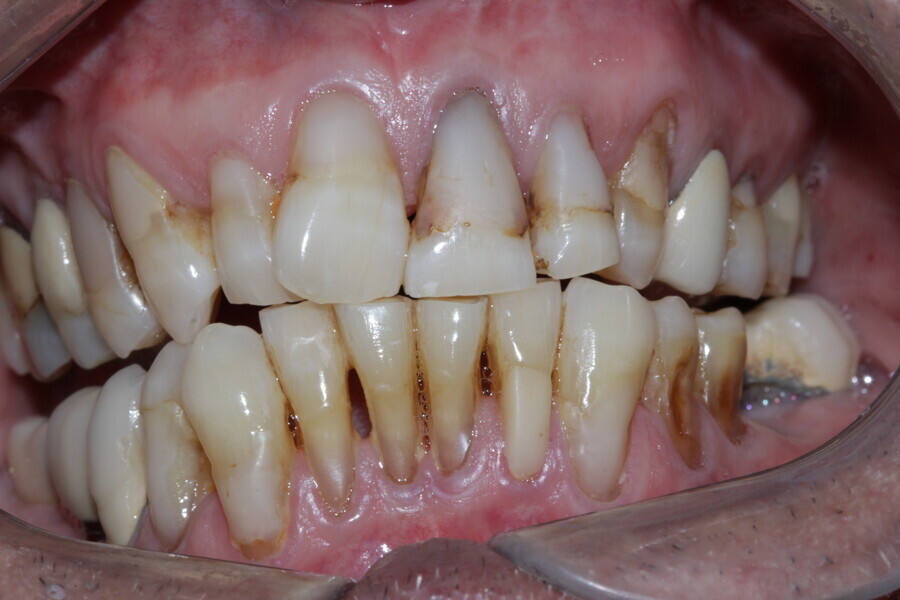

Figure 3 Anterior guidance before treatment